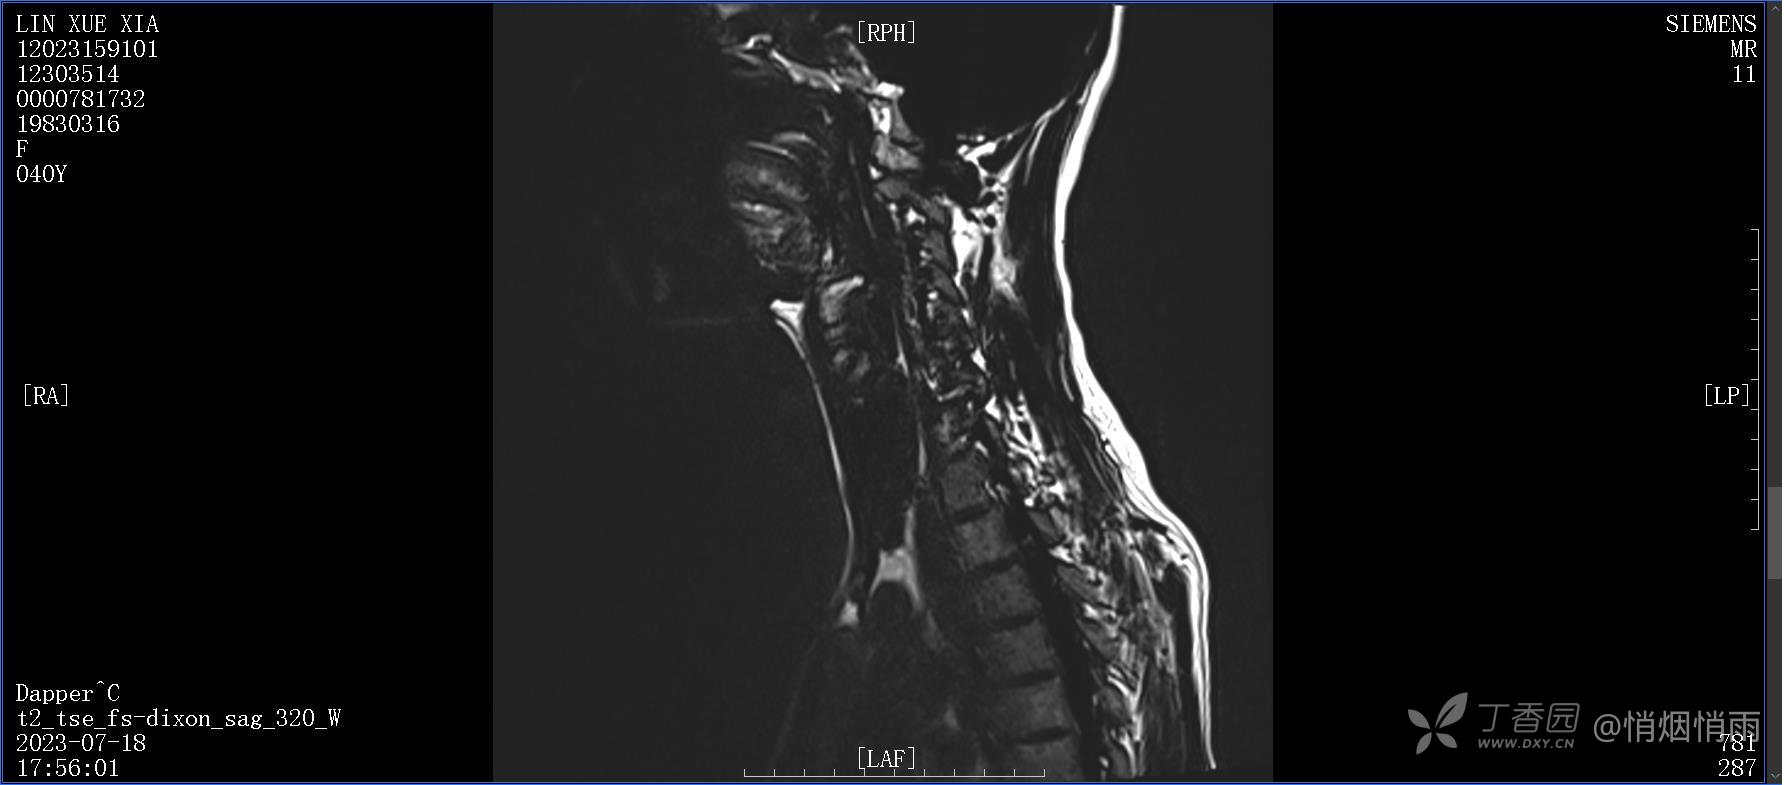

NeurothinkerZ 推荐患者女性,40岁,因右肩背部疼痛班活动受限4日余入院(2023-07-17)。

病史:入院前4天无明显诱因突然感右肩背疼痛伴随活动受限,自行口服依托考昔、艾瑞昔布等药物治疗,院外应用肩关节局部手法按摩等,均无明显改善。外院门诊诊为颈椎病。自诉既往多次“胸椎小关节紊乱”于当地诊所行手法按摩,治疗后好转,否认慢性疾病病史、外伤史、手术史,诉青霉素过敏,无其他药物食物过敏史,否认吸烟史、饮酒史,月经正常,经量正常。

目前的诊断,暂时依据辅助检查诊为肩袖损伤,但是患者疼痛的性质和特点,却不是单纯的肩袖损伤所致。考虑过胸廓出口综合征,但是该疾病会出现肩胛区的疼痛吗?(由于考虑到费用的问题,没再进行下一步的检查)带状疱疹会有如此的症状吗?